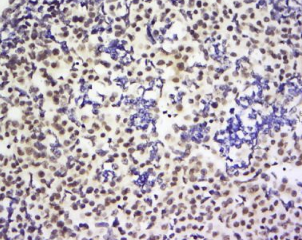

多聚甲醛固定,石蜡包埋(小鼠睾丸);用柠檬酸钠缓冲液(pH6.0)煮沸15min后获得抗原;用3%过氧化氢阻断内源过氧化物酶20分钟;阻断缓冲液(正常山羊血清)37℃30min;用BUB1多克隆抗体进行抗体孵育在4°C下1:200整晚未结合的全身,然后根据SP试剂盒(兔子)说明和DAB染色进行操作。